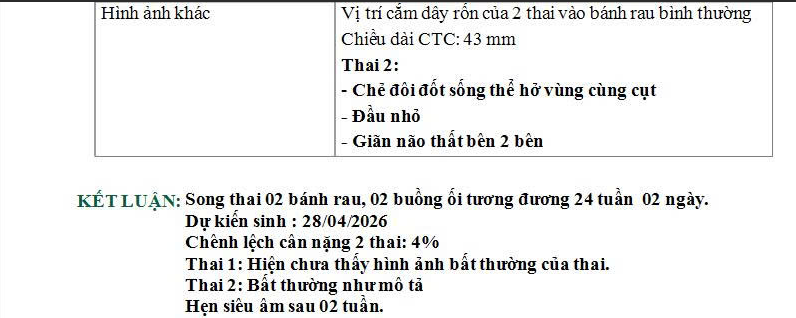

Chị H. mang thai 19 tuần, đến phòng khám Dr Tú y học bào thai với một tập hồ sơ khá dày. Trong đó có giấy siêu âm hình thái, phiếu xét nghiệm máu và usb chứa video siêu âm. Dòng kết luận khiến chị mất ngủ là nghi ngờ dị tật ống thần kinh, chẻ đôi đốt sống thể hở.

- Chẻ đôi đốt sống thể hở

Trong đó, chẻ đôi đốt sống thể hở là thể thường được phát hiện ở quý II.

AFP cao không đồng nghĩa chắc chắn dị tật. Thai đôi hoặc một số tình huống khác cũng có thể làm AFP tăng.

Nếu là chẻ đôi đốt sống thể hở, bác sĩ sẽ tập trung vào ba nhóm câu hỏi.

Tổn thương nằm ở đoạn nào của cột sống.

Có dấu hiệu kéo tụt hố sau và giãn não thất hay không.

Và dự kiến ảnh hưởng vận động, bàng quang–ruột ở mức nào.

Nếu tổn thương ở đoạn cao, nguy cơ ảnh hưởng vận động chi dưới thường lớn hơn. Nếu giãn não thất tiến triển, trẻ có thể cần đánh giá và can thiệp dẫn lưu dịch não tủy sau sinh. Nếu có bất thường kèm theo, cần mở rộng đánh giá di truyền và lập kế hoạch theo dõi sát hơn.

Vì vậy, mục tiêu của theo dõi trước sinh là xác định đúng thể tổn thương, mức tổn thương và tình trạng não thất theo thời gian. Mục tiêu sau sinh là phối hợp ngoại thần kinh, phục hồi chức năng và tiết niệu nhi để đánh giá chức năng thực tế và xây dựng kế hoạch chăm sóc dài hạn.